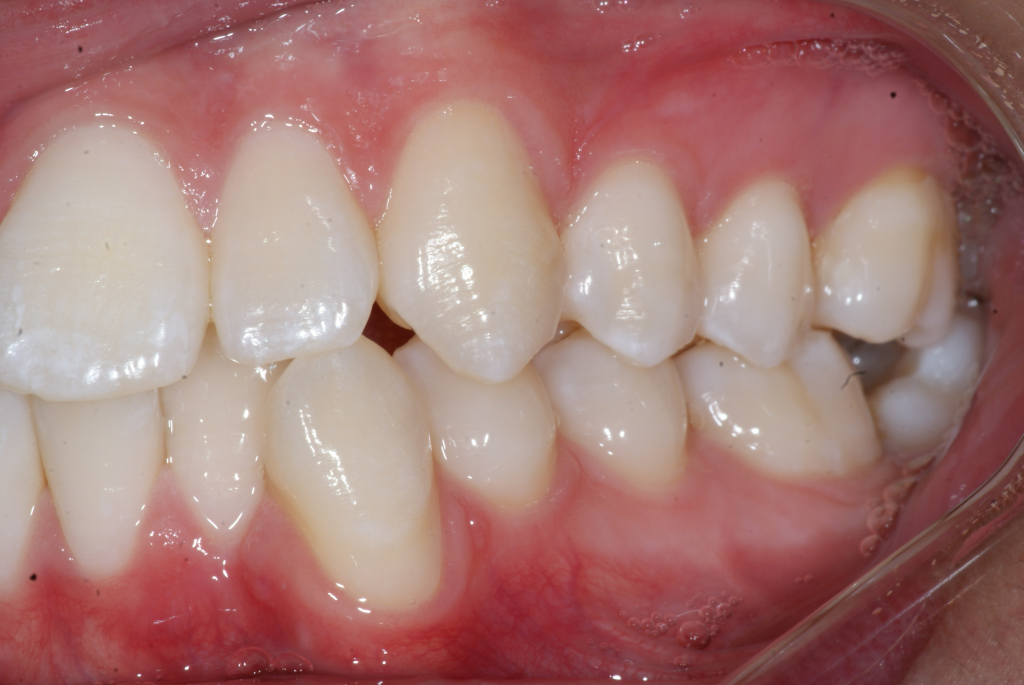

Correction d’une malocclusion de type bimax, canine #33 ectopique et chevauchement léger aux 2 arcades.  Des appareils fixes (broches) et extraction de 4 prémolaires furent nécessaires pour améliorer ce sourire.  Traitement chez un jeune adulte, réalisé en 28 mois.